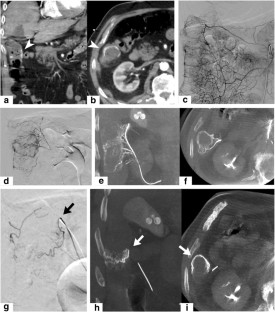

Fig. 2